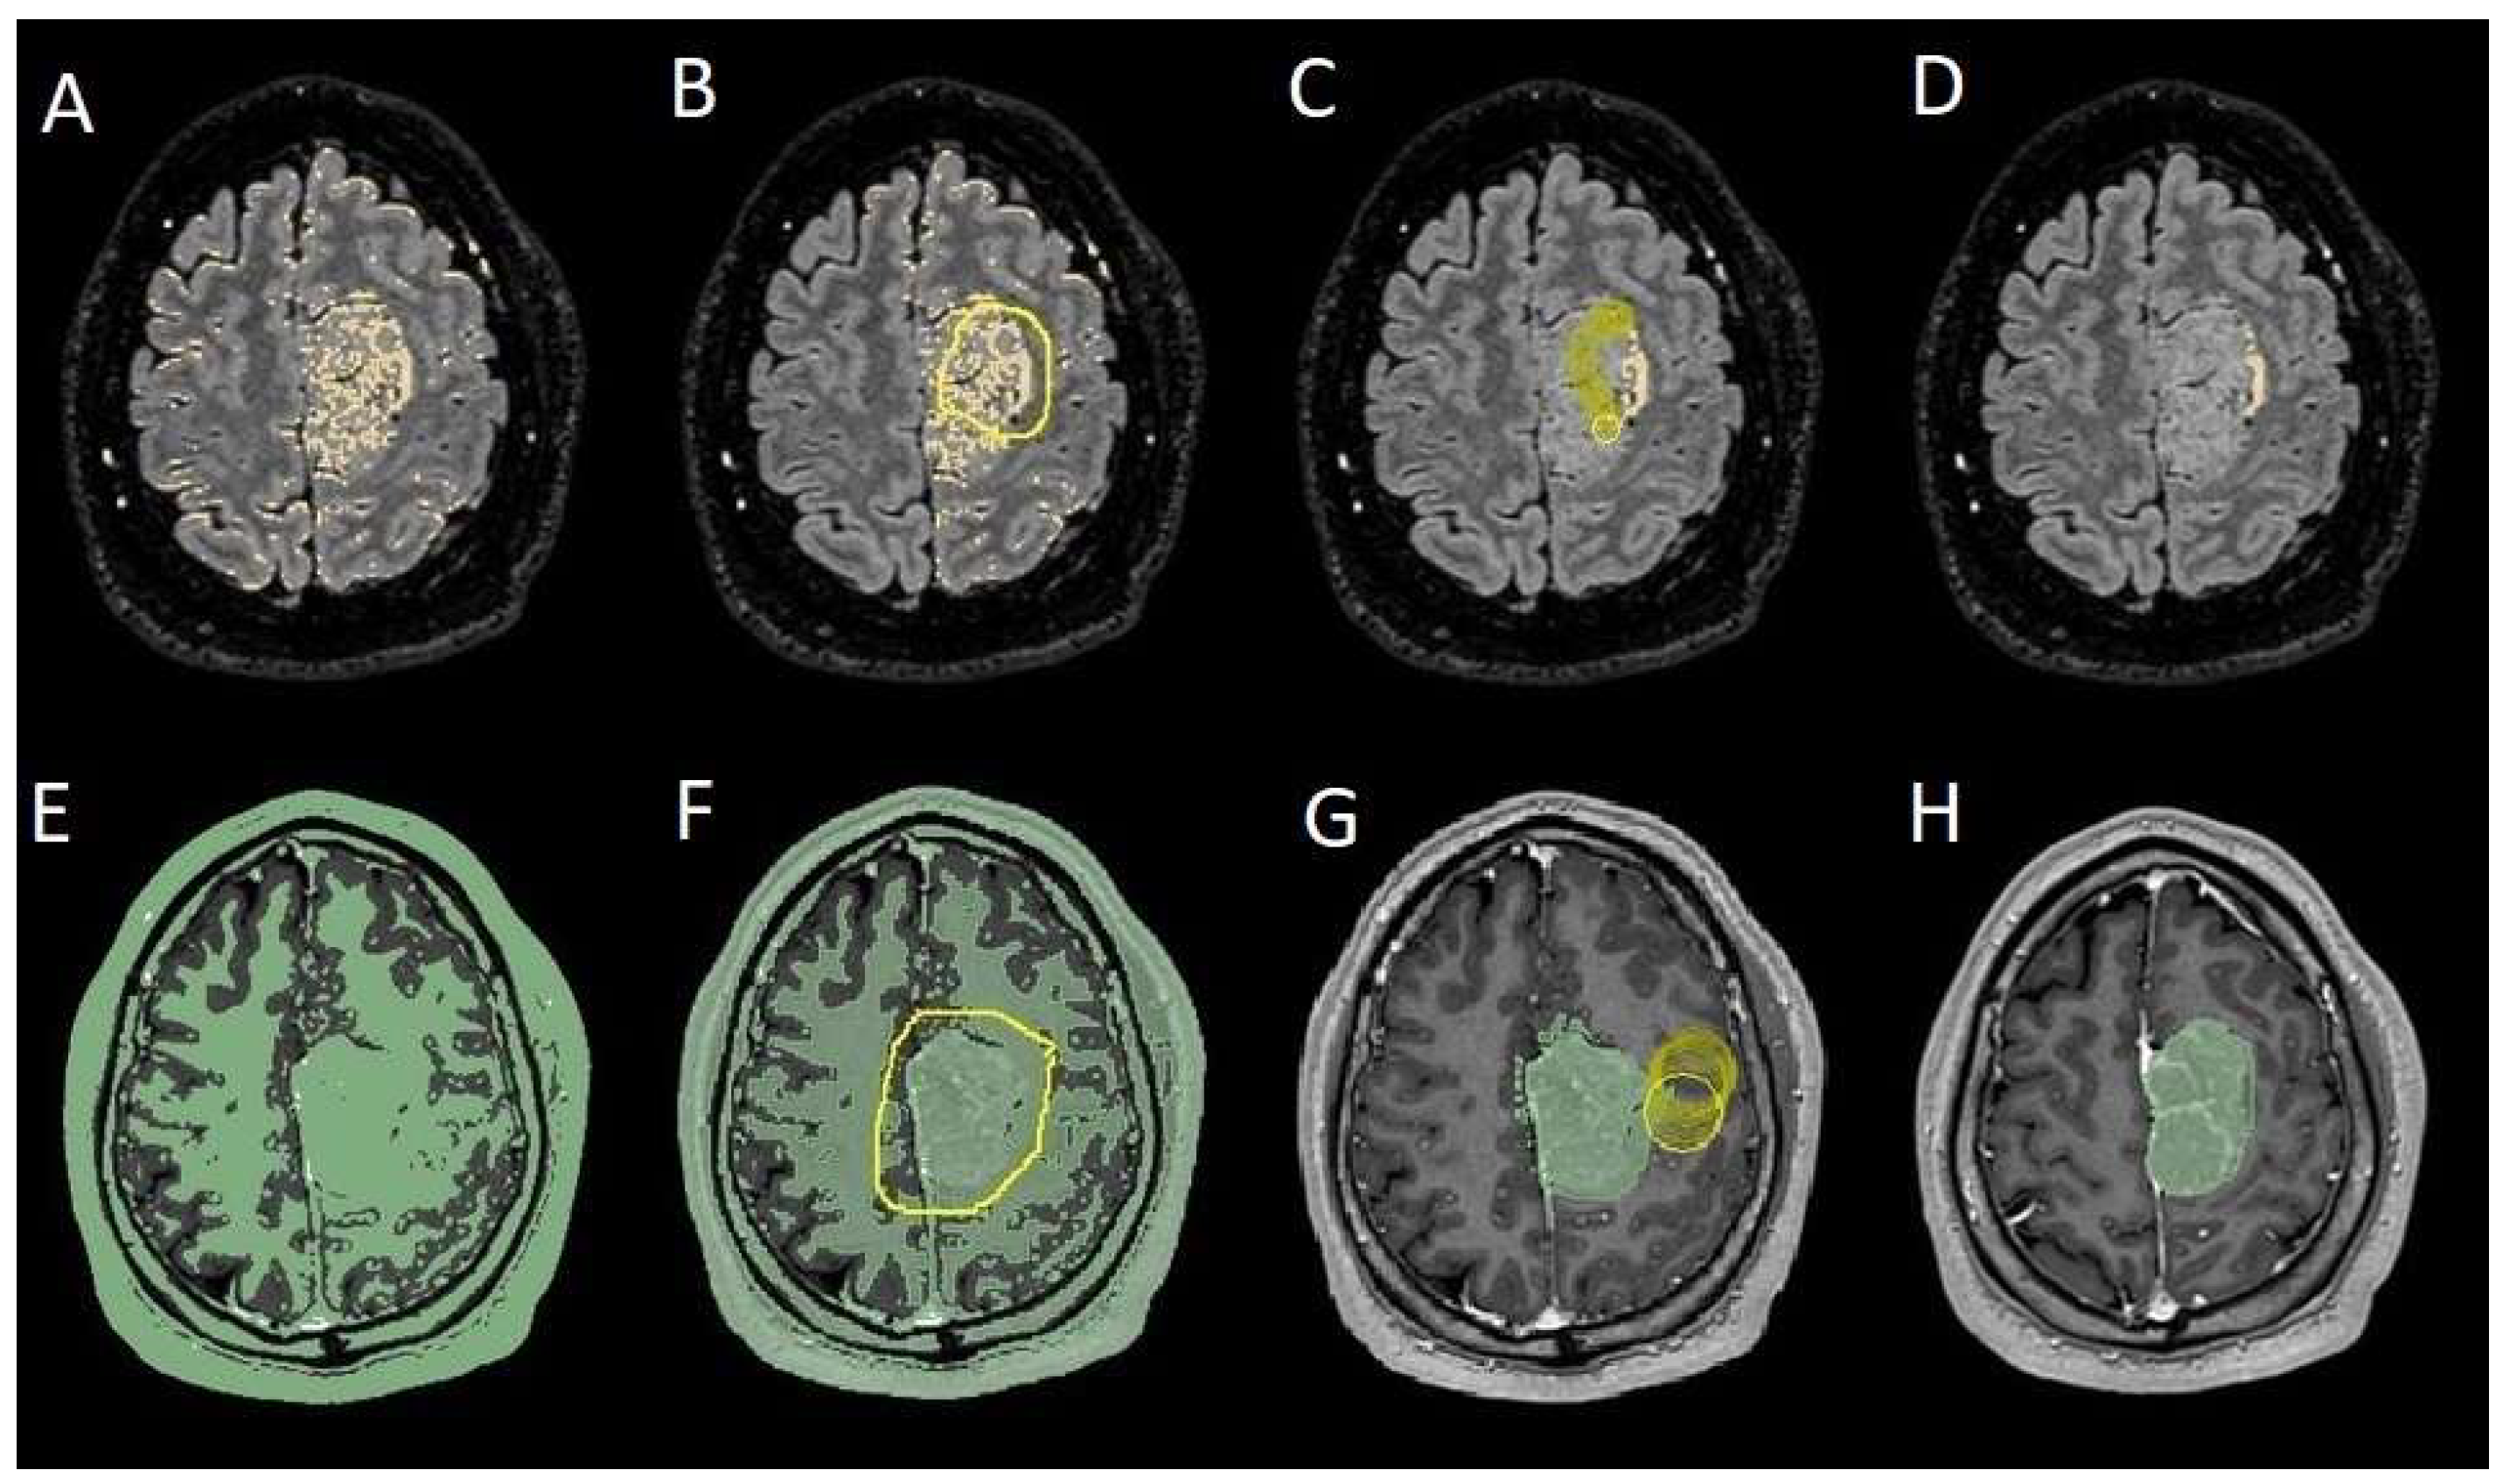

The patients underwent magnetic resonance imaging (MRI) at our center using a 1.5T or 3T Tesla MRI machine (Ingenia 3T, Philips Medical Systems, Best, The Netherlands) with the standard oncological protocol [14]. Specifically for analysis, the sequences collected were T1-weighted with contrast enhancement to estimate tumor volume and conformation and FLAIR (fluid-attenuated inversion recovery) to quantify PE (Figure 1). We manage the preoperative imaging in a DICOM (digital imaging and communications in medicine) format. The images from the T1-weighted sequences with contrast enhancement and FLAIR sequences in the DICOM format were processed through the Slicer website [15]. Tumor and PE segmentation was performed using a voxel-based analysis that integrated automated and manual methods (Figure 2).

The process begins with an automatic thresholding technique to identify initial regions of interest based on intensity values (Figure 2A,E). This is followed by manual refinement to enhance accuracy and delineate precise boundaries (Figure 2B,C,F,G). The final segmentation provides volumetric measurements for both the tumor and the PE, aiding in quantitative analysis (Figure 3). The included patients’ pre- and post-treatment clinical data were retrospectively extracted from our center’s computerized database. Collected data included demographic information, preoperative clinical details (presence or absence of epilepsy, onset symptoms, ASM therapy and number of ASMs taken, and radiological characteristics of the meningioma), and postoperative data (Engel class [16], persistence or discontinuation of ASMs, ASM discontinuation timing, and possible postoperative functional deficits). A single examiner conducted data collection to minimize subjective variability in assessments. Surgical procedures were performed using a transcranial approach under general anesthesia. We excluded cases of surgical resection performed via an endoscopic endonasal approach. Cases of postoperative death (within one year after surgery) were excluded. The extent of resection (EOR) was determined based on the postoperative MRI (usually one month after surgery) and classified according to the Simpson grading system [17]. This study included cases of complete macroscopic meningioma resection (Simpson I, II, and III). Cases with residual tumor persistence or recurrence after surgery (Simpson IV and V) were excluded (Figure 4).

Figure 2. Example of segmentation process with the Slices website. (A,E) Automatic thresholding technique to identify initial regions of interest based on intensity values, respectively, for the PE on the FLAIR sequence and the meningioma on the T1-weighted-with-gadolinium sequence. (B,F) Partially automatic erasure of redundant signal with “erase outside” tool. (C,G) Definition of boundaries of edema and tumor through manual erasure. (D,H) Final segmented volumes. FLARI: fluid-attenuated inversion recovery; PE: peritumoral edema.